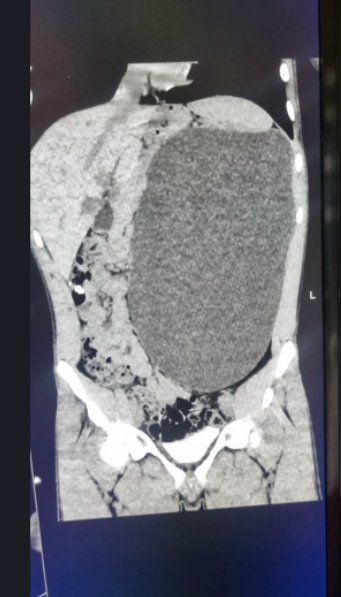

El joven, que se sentía completamente sano y nunca había tenido molestias, se sometió a un examen médico obligatorio previo a su contratación. Para su sorpresa, los médicos descubrieron que padecía hidronefrosis, una enfermedad que había inflamado su riñón izquierdo de forma descontrolada. El órgano ocupaba casi todo el abdomen y presionaba el resto de órganos.

“Era una verdadera bomba de relojería“, explicaron los especialistas del hospital. “Cualquier traumatismo, cualquier golpe accidental en el abdomen podría haber provocado una ruptura interna”. La enfermedad era asintomática y el chico ignoraba por completo el peligro.